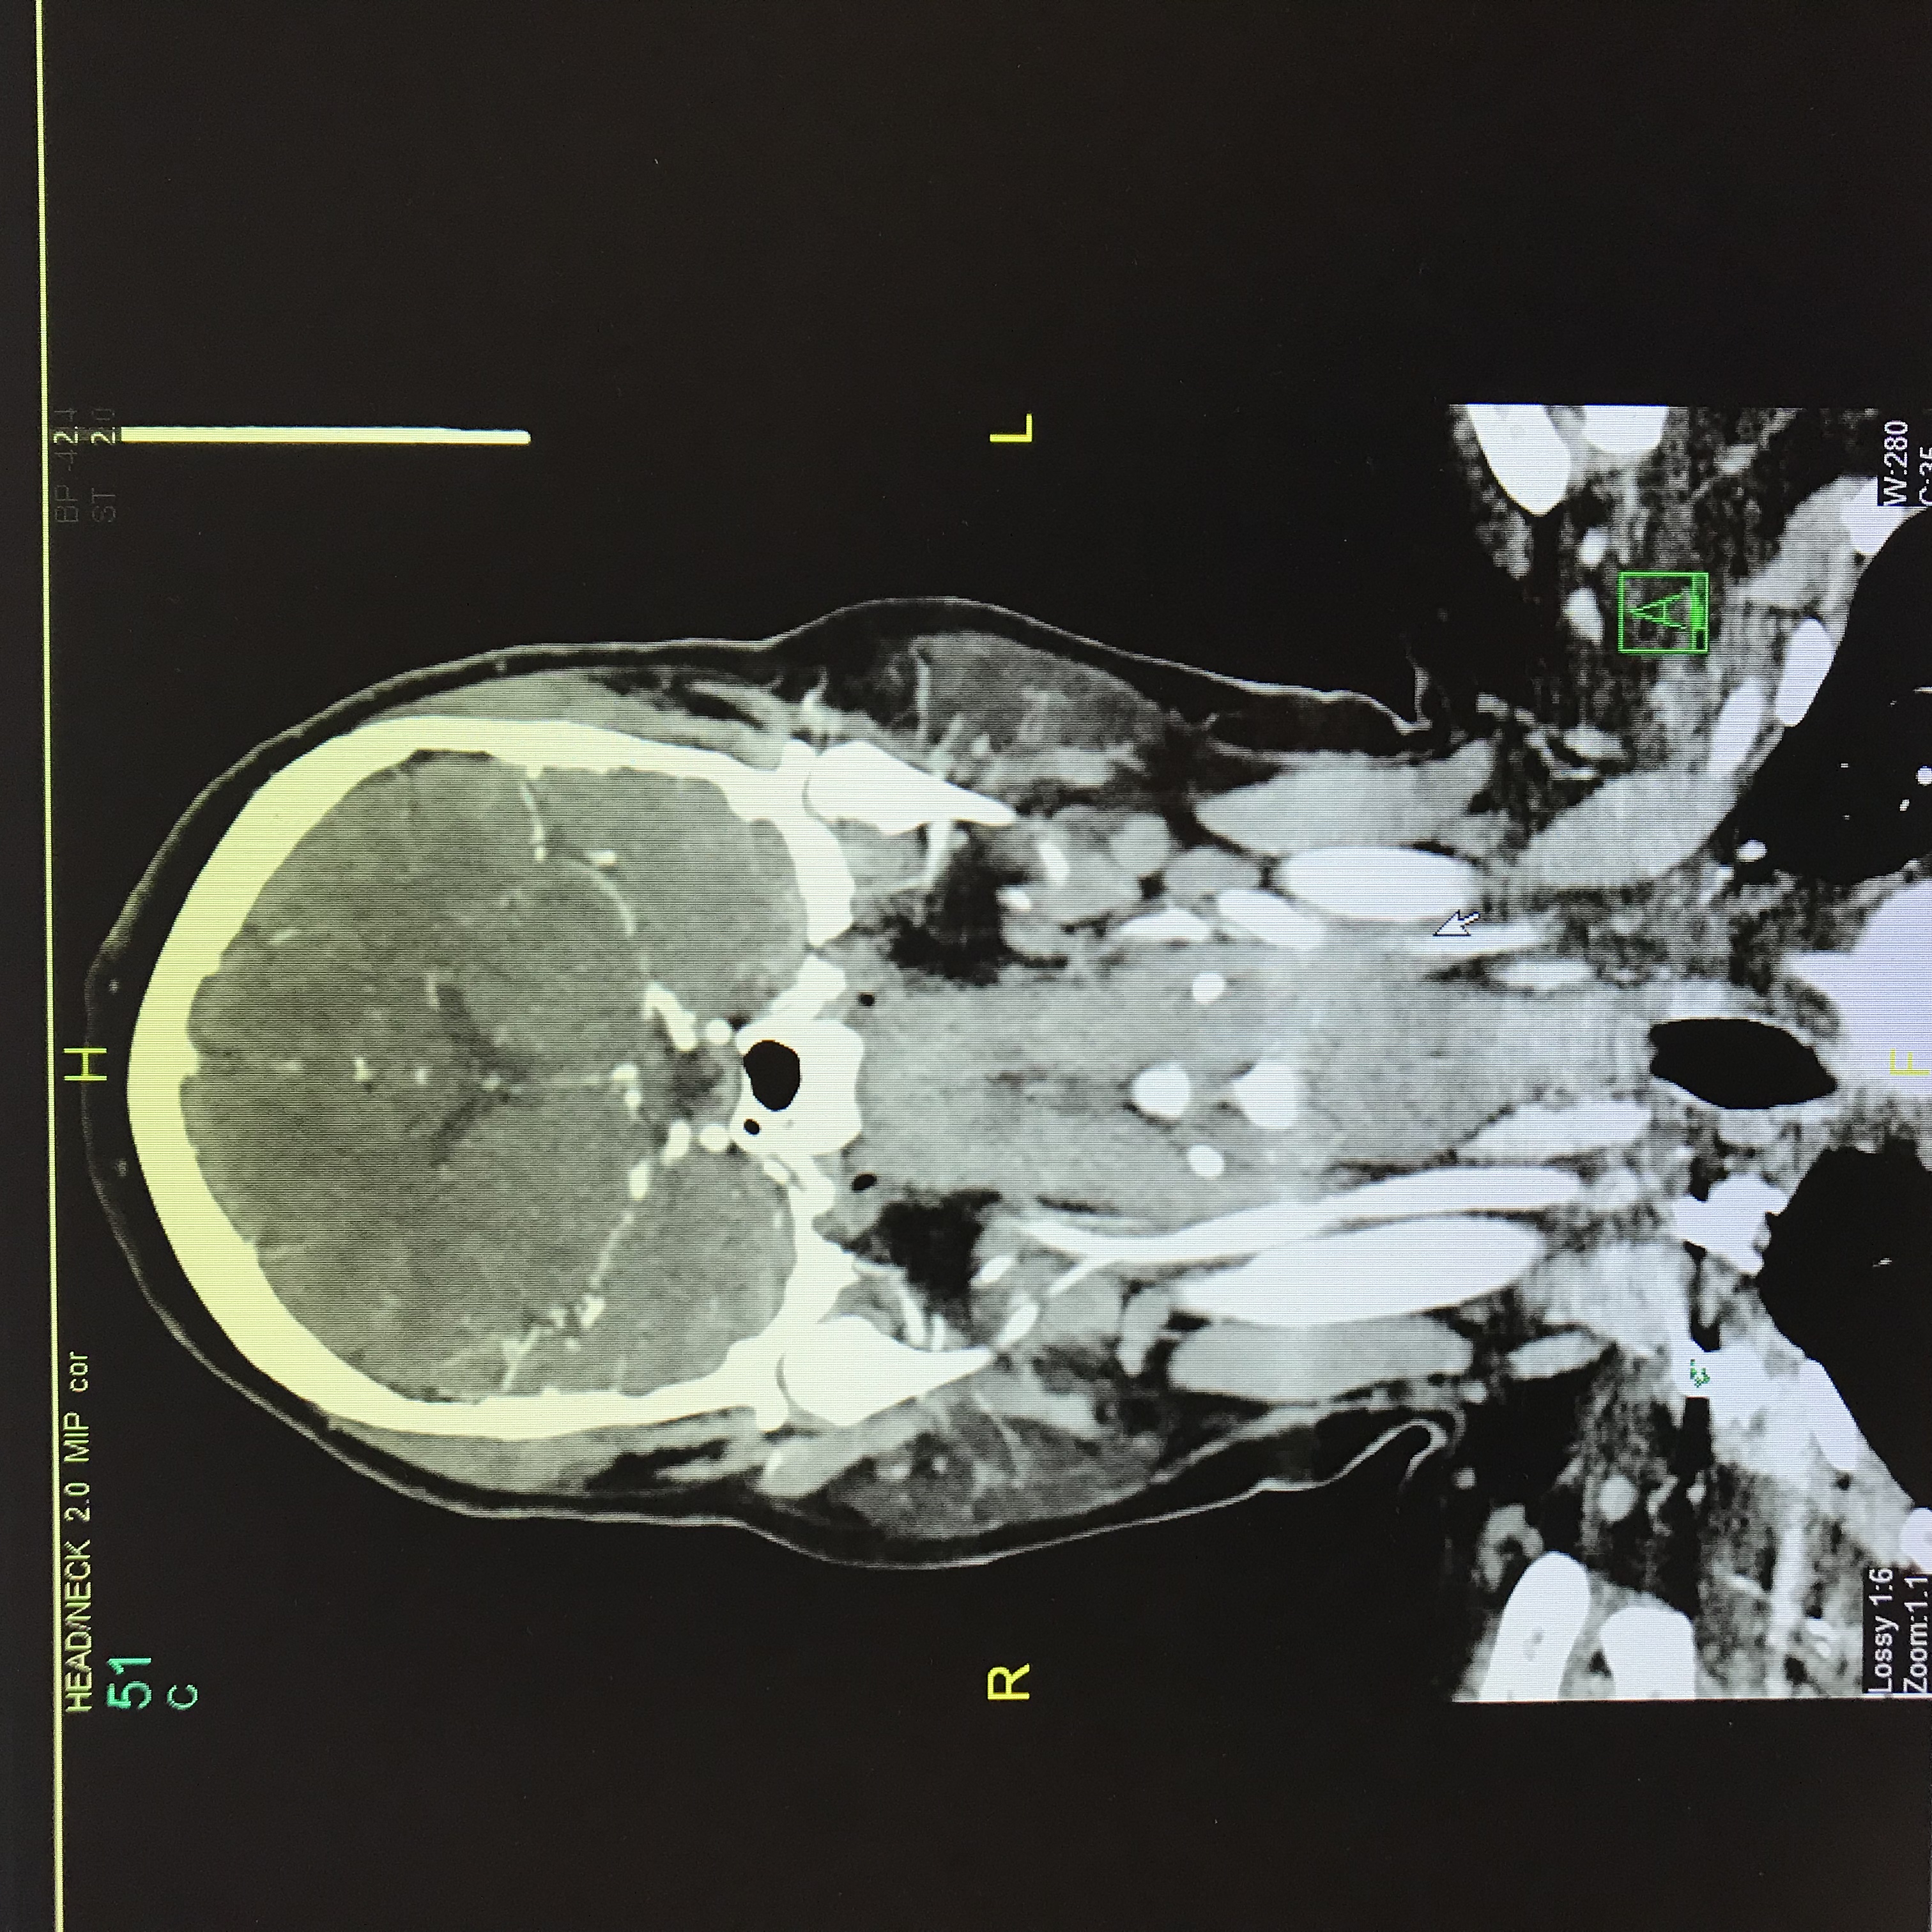

Discussion: This is a case of 49 year old Caucasian female patient with known past medical history of hypothyroidism who presented to the hospital emergency department with sudden onset of visual disturbances, severe headache, numbness and tingling sensation of her left arm. On further questioning, she described her visual disturbances of having black and silver floaters scattered throughout her visual field associated with pulsatile tinnitus and whooshing sensation in her ears. On physical exam, the National Institutes of Health stroke scale (NIHSS) was 0 on admission. CT head without contrast showed no evidence of acute intracranial hemorrhage or infarction. CT angiography showed narrowing of the right V4 segments of the vertebral artery along with beaded appearance of proximal left ICA suspicious for Fibro-muscular Dysplasia with no evidence of aneurysm, carotid or vertebral artery dissection. MRA abdomen was done which showed no involvement of the renal arteries. Neurosurgery evaluated the patient and recommended continuing aspirin, statin and follow-up as outpatient for close monitoring.